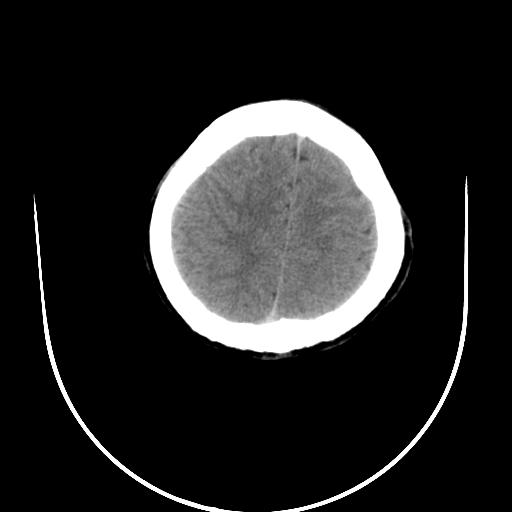

标题: CT10010:女/24岁,癫痫一周,发作时间不固定. [打印本页]

标题: CT10010:女/24岁,癫痫一周,发作时间不固定.

右侧额叶正常吗?

右额叶镰旁饱满.

右侧外侧沟?中央沟?可能有问题,不知以前有没有癫痫过,最好是增强下,排除局部血管畸形等病变

倒数第6幅图中线结构有点偏,而侧脑室额角未见异常,可结合增强扫描。